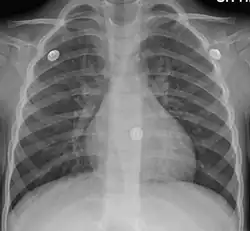

Вирусная инфекция является причиной более чем 90% случаев заболевания[9]. Бактерии встречаются лишь в 1 %—10 % случаев[10], однако их роль в развитии острого бронхита является спорной, поскольку бактериальная инвазия пока не обнаруживалась при анализе проб бронхиальной ткани[11]. Вирусы могут распространяться по воздуху при кашле или при прямом контакте[9]. Факторы риска включают воздействие табачного дыма, пыли и загрязнения воздуха. Небольшое количество случаев связано с высоким уровнем загрязнения воздуха или с бактериями, такими как Mycoplasma pneumoniae или Bordetella pertussis[12]. Диагноз обычно основывается на симптомах[13]. Цвет мокроты не указывает на вирусную или бактериальную инфекцию[14]. Определение патогена среди амбулаторных пациентов обычно не требуется[15]. Схожие с острым бронхитом симптомы могут быть и при других заболеваниях, которые включают в себя астму, пневмонию, бронхиолит, бронхоэктазы и ХОБЛ[16][17]. Рентген грудной клетки может быть полезен для выявления пневмонии.

Не существует каких-либо надёжных специфических тестов или диагностических признаков, с помощью которых можно установить диагноз острого бронхита[51][52]. Биомаркеры могут помочь в определении пациентов, для которых пользу могут принести антибиотики[15]. При подозрении на пневмонию может быть произведён тест на C-реактивный белок, а при сомнении в его результатах диагноз может быть подтверждён или отклонён с помощью рентгенографии грудной клетки[53]. Рентген грудной клетки полезен для исключения пневмонии у людей с лихорадкой, учащенным пульсом, учащенным дыханием или у пожилых людей, поскольку в этих случаях пневмония встречается чаще[17].